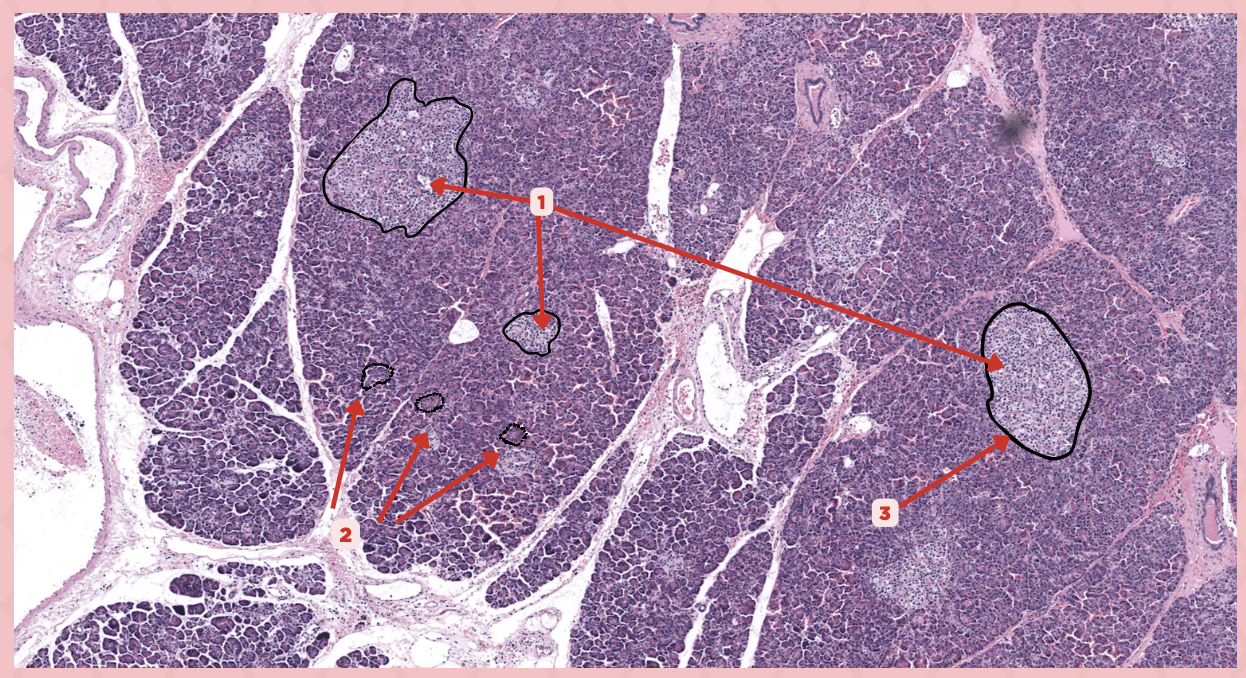

Parathyroid

Identify the specimen.

Chief Cells

Identify the specimen labeled as 1.

Oxyphil Cells

Identify the specimen labeled as 2.

Adipocytes

Identify the specimen labeled as 3.

Capillaries

Identify the specimen labeled as 4.

Newborns

Pointer #2 is hardly present in the parathyroid glands of _____.

Parathyroid

Identify the specimen.